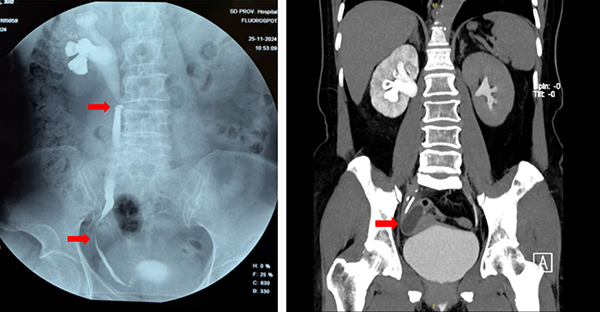

解女士因反复右下腹疼痛不适2年,曾于外院行输尿管镜检查,术中发现右侧输尿管下端明显狭窄,输尿管镜难以进入,无法进一步诊断和治疗。右下腹疼痛不适一直困扰着解女士,导致她无法正常工作和生活,慕名到院就诊。入院后,专家询问病史发现解女士既往曾两次行右侧卵巢手术,进行泌尿系增强CTU检查,结果显示右侧附件区见一类圆形无强化低密度囊性灶,截面约4.6*3.2cm,邻近右侧输尿管受压狭窄,其上游输尿管及右侧肾盂积水扩张。尿路逆行造影检查显示右输尿管两处狭窄:上段输尿管迂曲狭窄;下段输尿管可见因右侧附件区囊性肿物压迫导致狭窄。

左图红色箭头处提示右输尿管两处狭窄;

右图红色箭头处提示右侧卵巢囊肿压迫输尿管